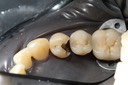

Alan Chinn #31 pre-op

Alan Chinn #31 caries removal

Alan Chinn #31 prep

Alan Chinn #31 model

Alan Chinn #31 finish